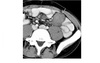

26

Small bowel spiculated mesenteric mass with calcification. Solidary enhancing ileal lesion

Carcinoid Sunburst desmoplastic reaction in the mesentery Tethering of SB loops 90% arise in terminal ileum/appendix Hyper-vascular liver mets - Carcinoid syndrome **111I- Octreotide scans (1st - highest sensitivity) or 123I-MIBG (for 10% dont take up octreotide) for Dx and staging** Assocaited with MEN 1 or MEN 2a DDX Sclerosing mesenteritis - FAT HALO sign - Mass envelop vessels, but preservation of fat around vessels - usually jejunal small bowel mesentery Gastrointestinal Stromal Tumor (GIST) - Hypervascular tumor, not associated with desmoplastic effect on mesentery Small Bowel Carcinoma - More common in duodenum or jejunum than in ileum - Causes luminal obstruction - Mass and metastases are hypovascular